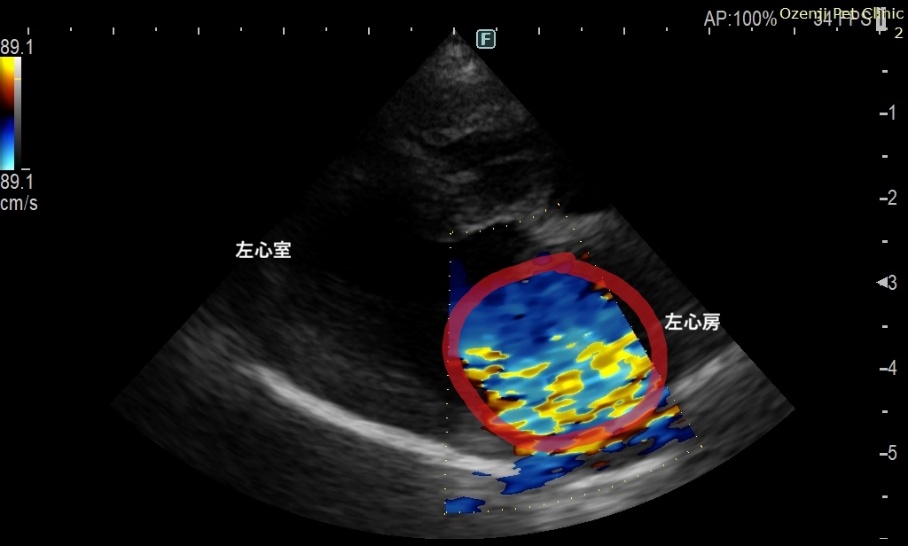

心臓は4つの部屋に分かれていますが、そのうちの左心房と左心室を隔てているのが「僧帽弁」で、血液の逆流を防いでいます。本来薄い僧帽弁の先端が腫れてしまう「粘液腫様変性」と呼ばれる変化が起きると、弁がうまく閉じなくなり、左心房から左心室へ流れるはずの血液の一部が左心房へ逆流します。この僧帽弁逆流は、聴診器で聞き取ることができます。